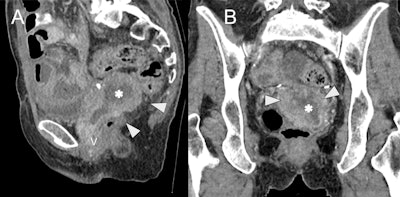

Cystic/necrotic pelvic mass mimicking hydro/hematometra in a 65-year-old female with recurrent ovarian cancer post total abdominal hysterectomy and bilateral salpingo-oophorectomy. Sagittal (A) and coronal (B) contrast-enhanced CT images demonstrate a soft tissue mass (white arrowheads) with central hypodensity, suggestive of cystic/necrotic component (asterisk). The mass is inseparable from the vaginal cuff (V) and mimics an obstructed, retroverted uterus, but instead represents local recurrence post hysterectomy.